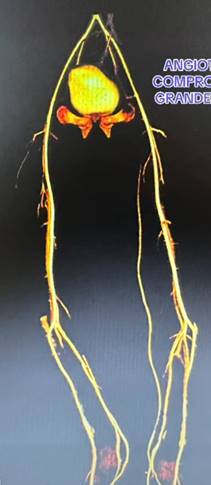

Se practica ecografía Doppler en modo B, con transductor lineal, a través del cual se detecta abundante contenido hemático en compartimiento anterior y lateral de la pierna, con imagen característica de quistes multitabicados Figura B, además se realiza una flebografía ascendente en la cual se evidencia que no existen fistulas arteriovenosas Figura C. En la Angiotac se descarta dependencia o comunicación con grandes vasos Figura D, por tanto, se diagnostica Malformación Vascular: Linfangioma.

Figura C. Angiotac sin compromiso de Grandes Vasos de Pierna Derecha.